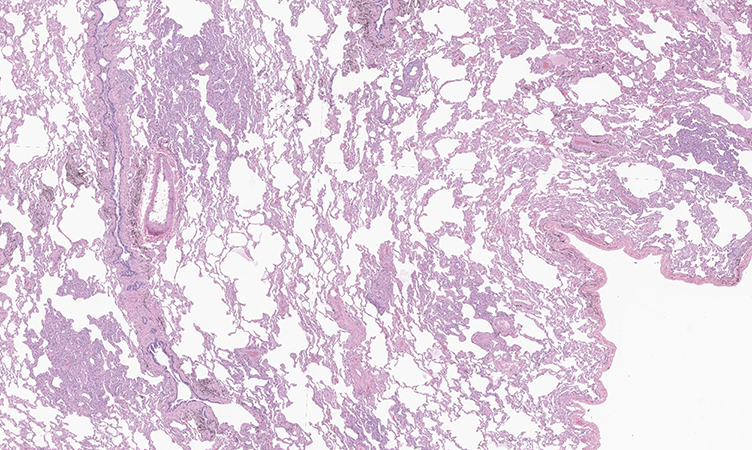

Histologically, MMPH consists of multicentric, nodular, well-defined proliferations of cuboidal pneumocytes along the alveolar walls (figures 1 and 2). The pneumocytes exhibit only mild cytologic atypia with preserved nuclear to cytoplasmic ratios (figures 3 and 4). Septal thickening associated with increased elastic fibers is a characteristic finding and can be highlighted with the use of elastic fiber staining. TTF-1 and Napsin A immunohistochemical stains are positive, consistent with the pneumocytic origin of MMPH, but melanocytic (HMB45, MelanA, MITF) and hormonal (ER, PR) markers are negative, unlike in LAM.

Clinical History: A 35-year-old man, former light smoker (2 pack-years), with a history of tuberous sclerosis and amyloidosis with associated end-stage renal disease, presented with multiple bilateral ground glass pulmonary nodules detected on a chest-CT scan, which was done as part of renal transplant work-up. A right upper lobe wedge resection was performed (see figures 1 through 4).